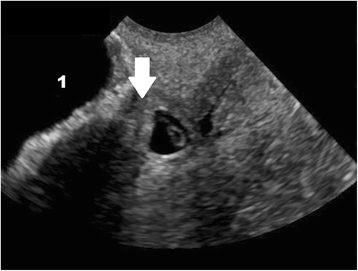

In women presenting with bleeding or pain, pregnancy location is often not definitively visualized on the initial ultrasound at presentation; however, diagnosis of EP by ultrasound is possible when following careful guidelines. Identification of a gestational sac and fetal pole, with or without cardiac activity, or a hyperechoic ring—called the ‘bagel’ or ‘tubal’ sign (Fig. 1)—with circumferential Doppler flow (Fig. 2) is highly suggestive of an ectopic pregnancy [95, 96]. If a suspicious mass moves separately from the ovary—called the ‘blob’ sign - the positive predictive value is above 90 % in a symptomatic woman with a positive serum b-hCG and no IUP on transvaginal ultrasound [97, 98].

Ultrasound criteria for diagnosis of an interstitial ectopic pregnancy include a gestational sac at least 1 cm lateral to the edge of the uterine cavity, with a thin (5 mm or less) layer of overlying myometrium surrounding it (Figs. 3 and 4) [99, 100]. An ‘interstitial line’ may also be seen (Fig. 5) [101].

Interstitial ectopic pregnancy by transvaginal ultrasound. The arrow indicates thin (<5 mm) myometrium overlying the ectopic pregnancy. This finding by ultrasound, in combination with the lateral location of the gestation, has a reported specificity of 88-93 % but a sensitivity of just 40 % [101].